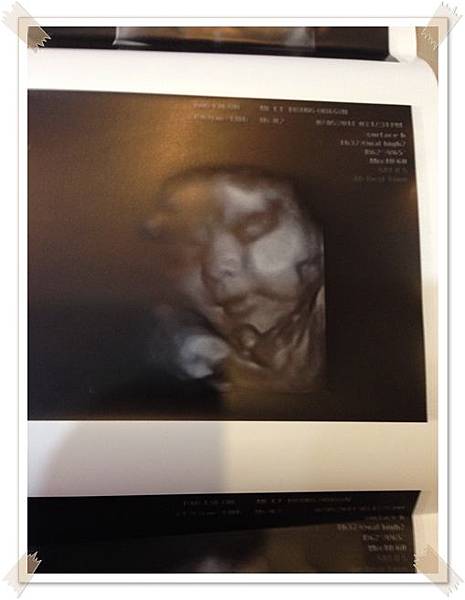

索性跑去社團媽媽很推薦的一家照4D很清楚的婦產科檢查

醫生挺有耐性的 , 大概照了10-20分鐘 ,也量了一下寶寶現在的體重大約2400g了

拿到照片好開心 ,因為第一次這麼清楚的看到寶寶的臉

醫生還說寶寶輪廓有爸爸的影子orz